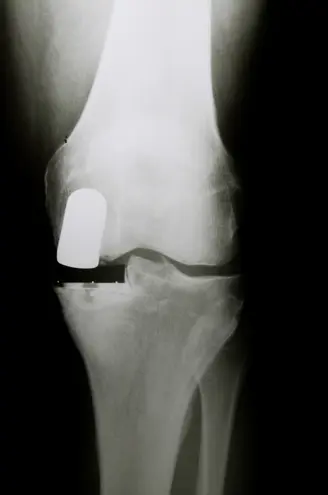

Your knee is divided into three major compartments Ghoota's expertise and the hospital's dedicated team. The medial compartment (the inside part of the knee), the lateral compartment (the outside part), and the patellofemoral compartment (the front of the knee between the kneecap and thighbone)

In a unicompartmental knee replacement, only the damaged compartment is replaced with metal and plastic.

Partial knee replacement is a surgical option if your arthritis is confined to a single compartment of your knee Unicompartmental knee replacement is a minimally invasive surgery in which only the damaged compartment of the knee is replaced with an implant. Exercise resources testimonials, videos, podcasts and more Knee partial knee replacement surgery this video shows a partial knee replacement surgery